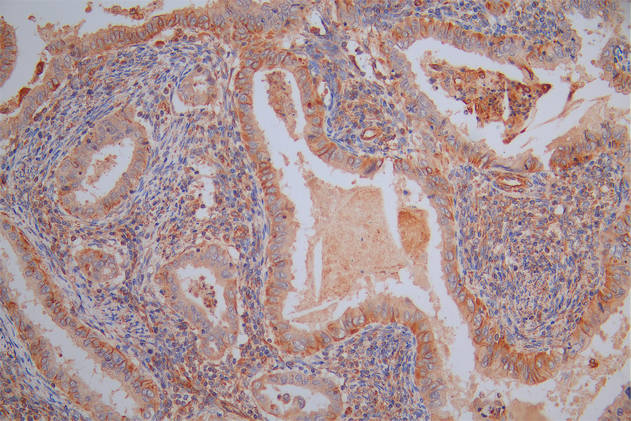

Immunofluorescence staining of Hela cells with CSB-PA859103LA01HU at 1:100, counter-stained with DAPI. The cells were fixed in 4% formaldehyde, permeabilized using 0.2% Triton X-100 and blocked in 10% normal Goat Serum. The cells were then incubated with the antibody overnight at 4°C. The secondary antibody was Alexa Fluor 488-congugated AffiniPure Goat Anti-Rabbit IgG(H+L).